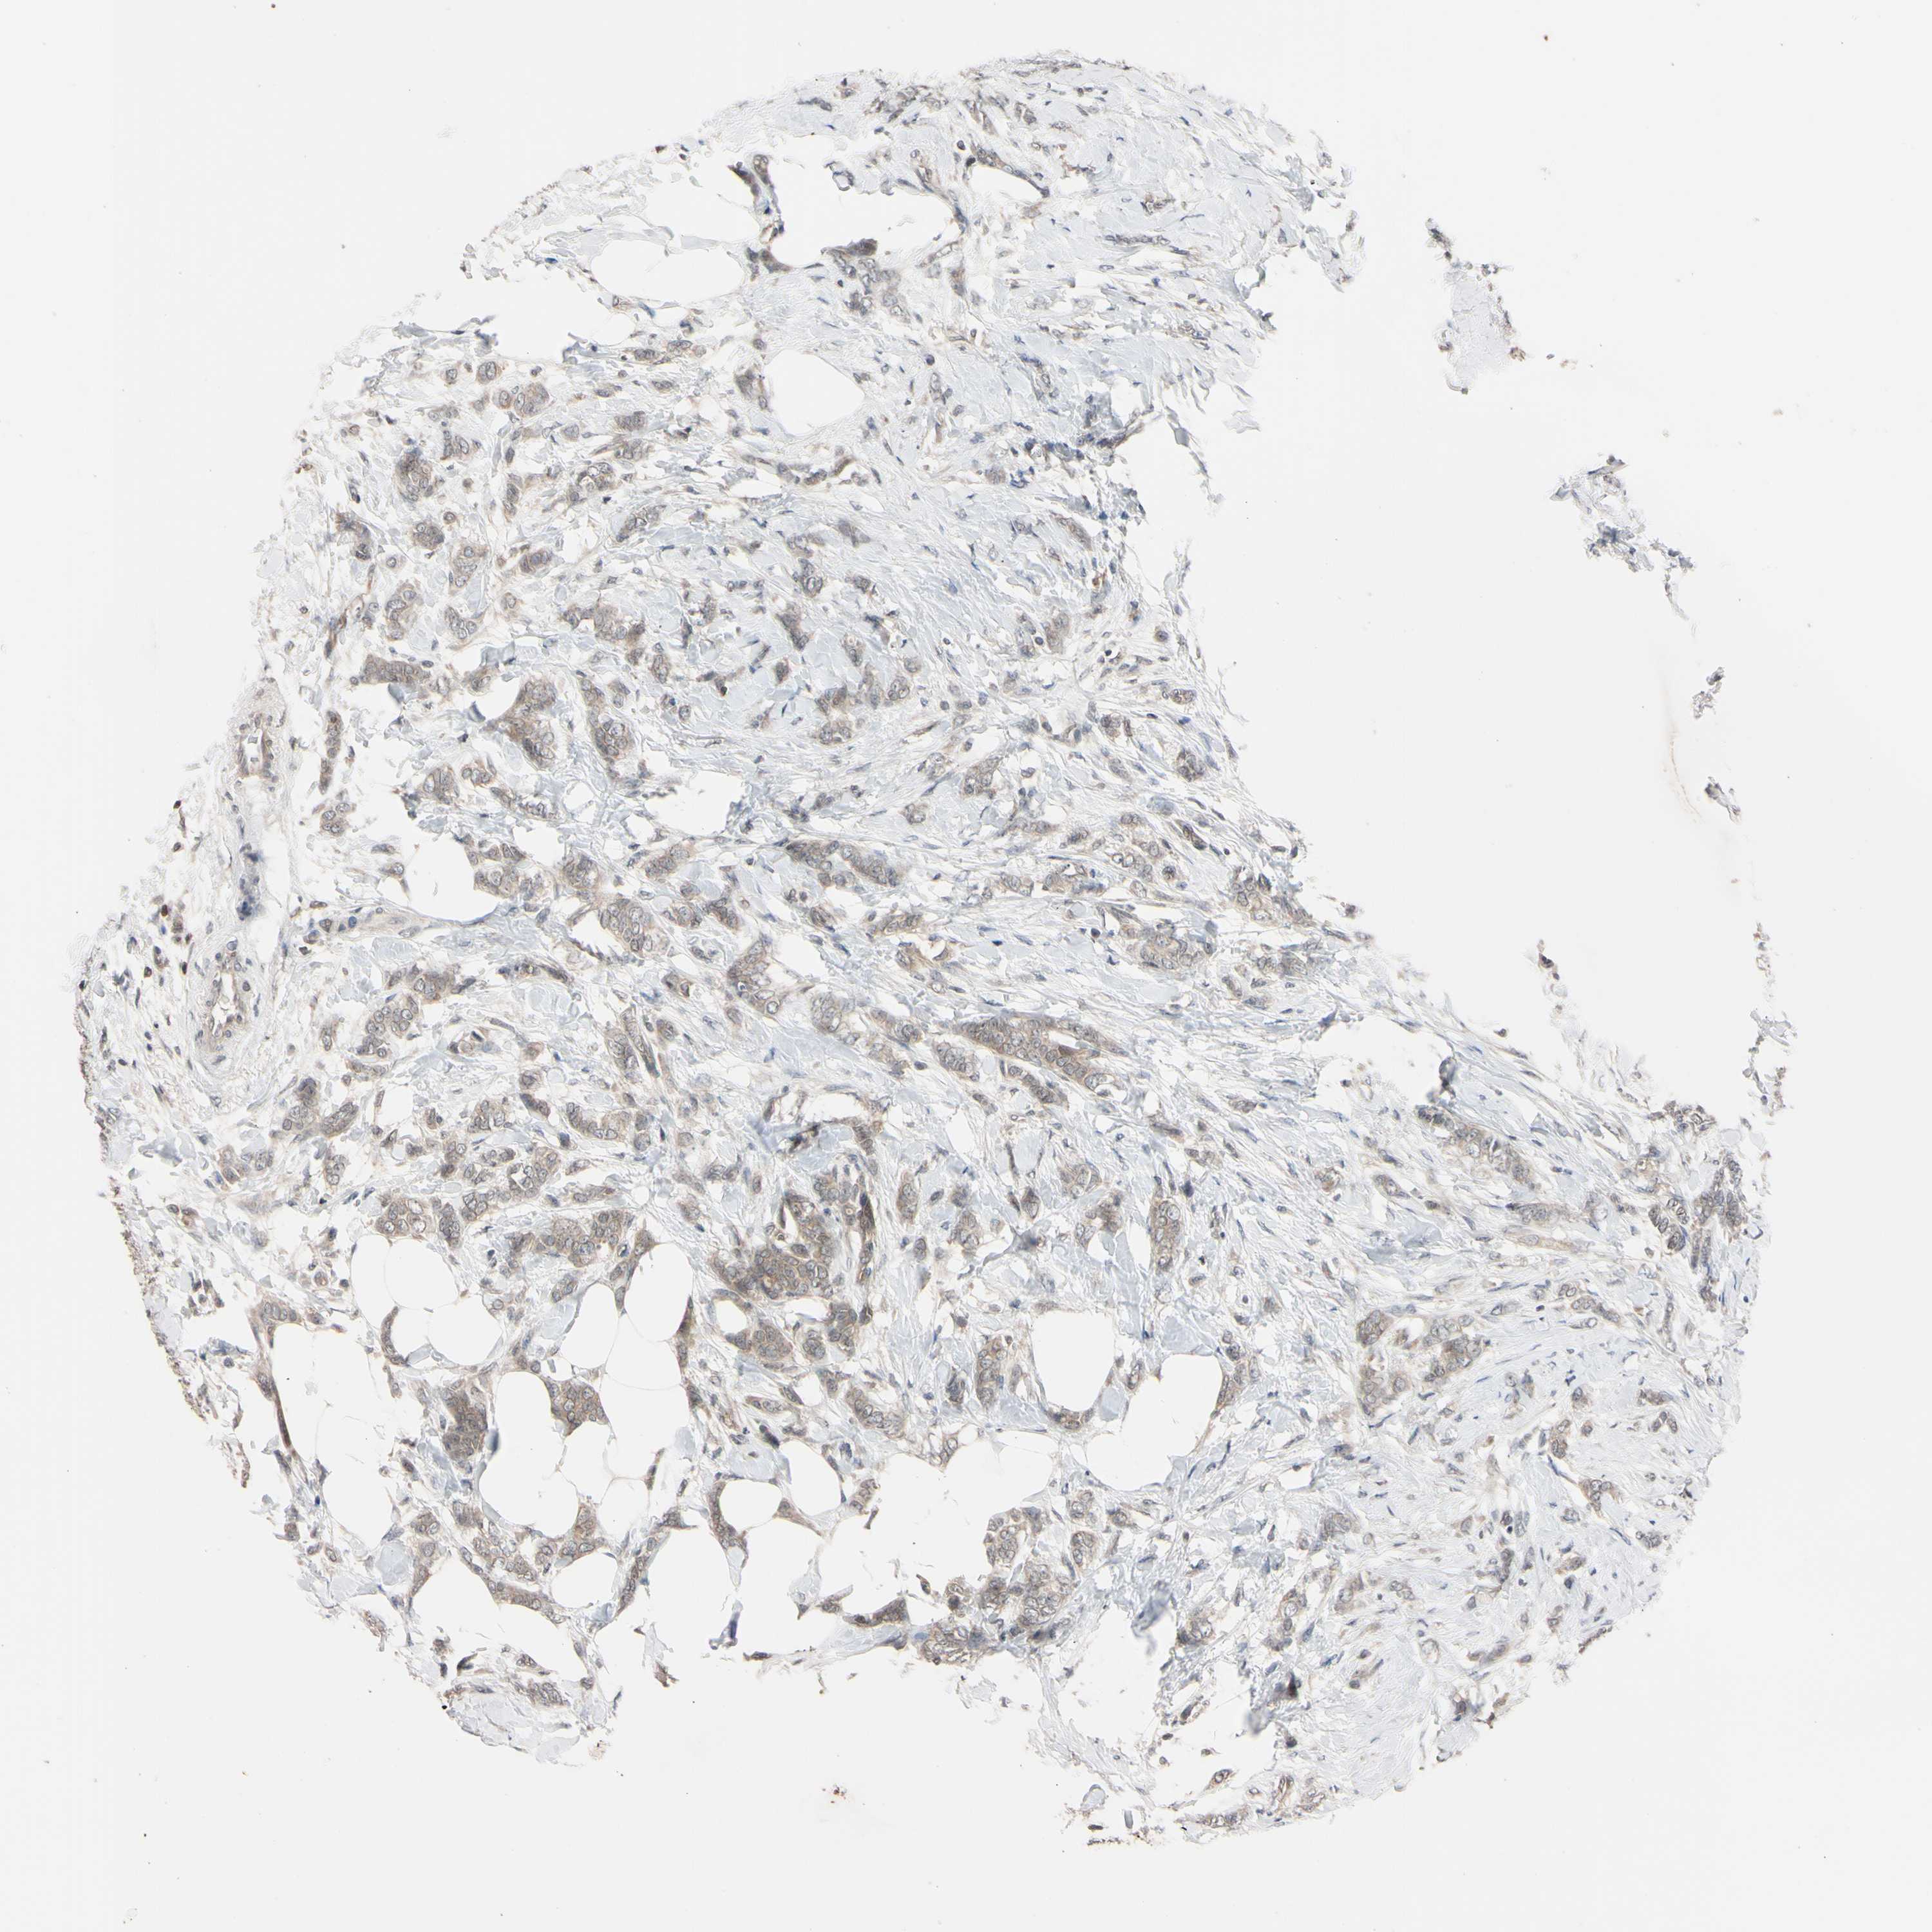

CANCER BREAST CANCER Show tissue menu

BRCA TCGA BRCA VALIDATION PROTEIN EXPRESSION